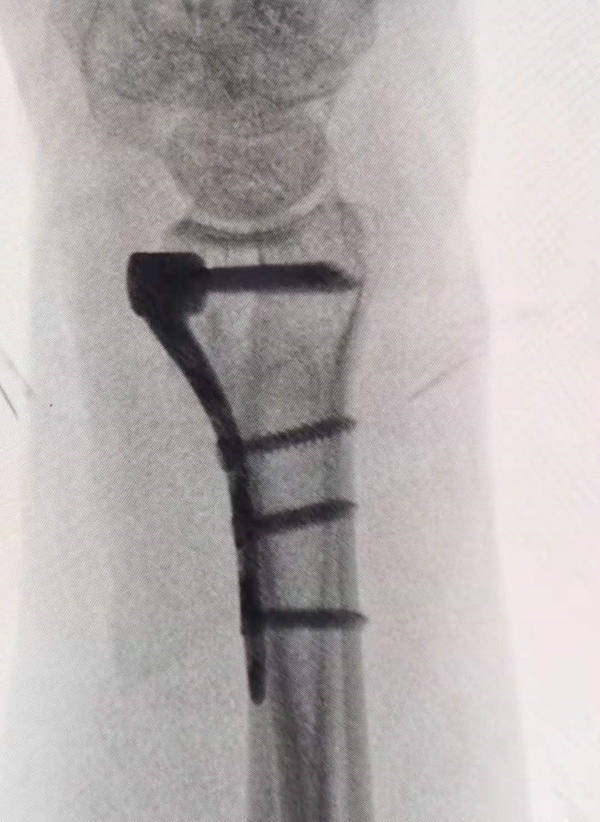

图2 掌倾角欠妥

②尺偏角:桡骨尺侧乙状切迹的中点与桡骨茎突最高点的连线,同桡骨长轴垂线之间的夹角即为尺偏角,平均值为24°,小于15°具有手术指征。

③桡骨高度:首先作两条垂直于桡骨长铀的平行线,一条通过桡骨茎突的尖端,另一条通过月骨窝的尺侧角,这两条平行线之间的距离就是桡骨高度,平均12 mm,该值的测量用于判断桡骨的短缩程度。

图3 尺偏角及桡骨高度恢复